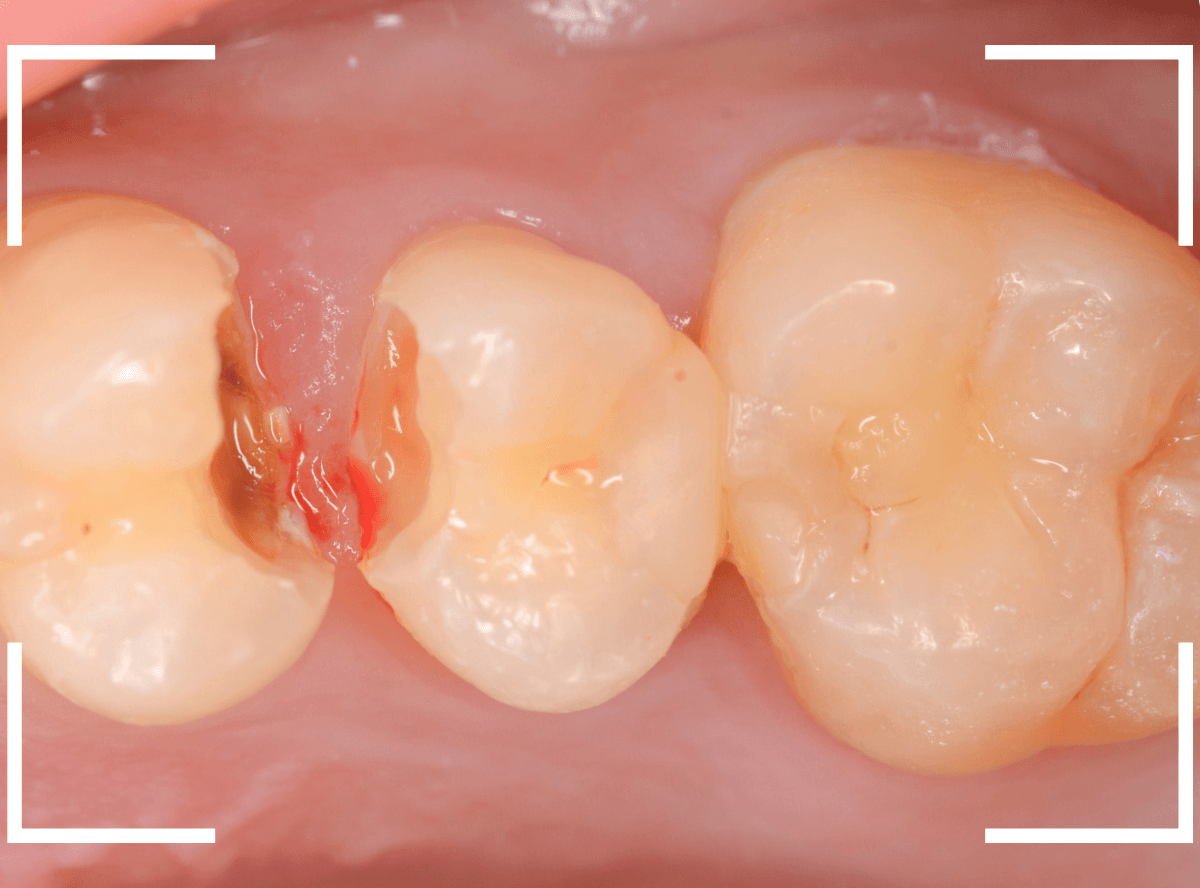

Case.15 レジンの下の深い虫歯

奥歯で咬んだ時に、痛みを感じるという訴えで来院された患者さんです。

パッと見は特に問題なさそうな状態ですが、大きなレジン治療がしてあり、レジンの奥もボヤっと黒っぽく見えてアヤシイ感じです。

麻酔をして、レジンを外します。

レントゲン写真から想定できるような大きな虫歯ですね。

慎重に虫歯を除去します。

赤く染色されている部分が虫歯の残っている部分です。

全ての虫歯を除去したところです。

何とか神経の寸前で虫歯を食い止める事ができましたが、まれに症状が出る事もありますのでお薬をつめてしばらく経過観察します。